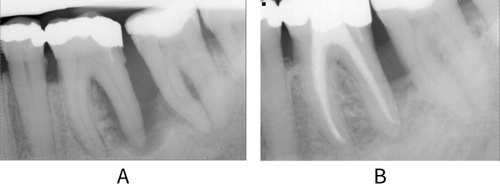

A: Periapical radiograph before treatment showing bone loss extending to the apex and into furcation around tooth 36. This was managed by a combination of endodontic and non-surgical periodontal treatment. B: Image after treatment shows good quality root filling and bone infill around the distal root of 36.

Combined endodontic-periodontal lesions occur where a patient not only has clinical attachment loss but also a tooth with a necrotic, or partially necrotic, pulp (see Other periodontal conditions). Pulpal damage may occur as a result of exposure of accessory canals in patient with a diagnosis of periodontitis, or the lesion may be associated with damage to the root or root surface itself, independent of periodontal disease. These lesions can be difficult to diagnose, therefore a clinical examination and the use of special tests (radiographs and vitality tests) are required to assess both the periodontal (swelling, bleeding or suppuration, increased probing pocket depth) and endodontic (presence of root damage or perforation, pulpal status, presence of fistula, tenderness to percussion) signs (see figure: Endodontic-periodontal lesion).